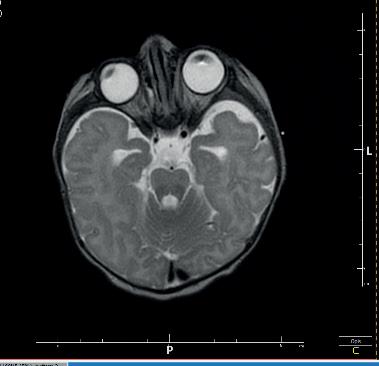

Kolejną interesującą publikacją jest artykuł Studium przypadku zespołu mozaikowej trisomii chromosomu 9 prof. Lidii Perenc z Instytutu Nauk o Zdrowiu Uniwersytetu Rzeszowskiego i współautorów. Zespół mozaiki trisomii 9 został opisany w 1973 roku przez amerykańskiego genetyka R. Haslama; w aktualnych danych uzyskanych z portalu orpha.net zaliczany jest do chorób rzadkich. W artykule omówiono przypadek kliniczny mozaikowej trisomii chromosomu 9 u niemowlęcia płci męskiej. Autorzy wskazują, że dla ustalenia prawidłowego rozpoznania należy uporządkować dane uzyskane na podstawie wywiadu, badania przedmiotowego i badań dodatkowych. W przypadku podejrzenia nieprawidłowego genotypu jako czynnika etiologicznego należy wykonać odpowiednie badania genetyczne. Warto również porównać obraz kliniczny i historię choroby pacjenta z danymi przedstawionymi w literaturze.

Another interesting publication is the article Case study of mosaic trisomy 9 syndrome by Professor Lidia Perenc from the Institute of Health Sciences at the University of Rzeszów and co-authors. Mosaic trisomy 9 syndrome was described in 1973 by American geneticist R. Haslam, and is classified as a rare disease in current data obtained from the orpha. net portal. This article discusses a clinical case of mosaic trisomy 9 in a male infant. The authors point out that in order to establish a correct diagnosis, the data obtained from the history, physical examination and additional investigations should be sorted out. If an abnormal genotype is suspected as an aetiological factor, appropriate genetic tests should be performed. It is also worth comparing the patient’s clinical picture and medical history with data presented in the literature.